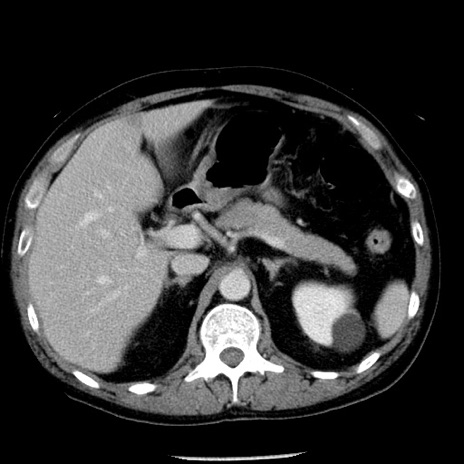

症例29(横断像)

【症例】40歳代男性

【現病歴】2日前から胃痛あり。徐々に周期的な激痛に変化した。本日になっても激痛があるため受診。

【身体所見】意識清明、BT 38-39℃台あり、腹部:膨満、やや硬、右下腹部に圧痛あり。

【データ】WBC 8500、CRP 23.26